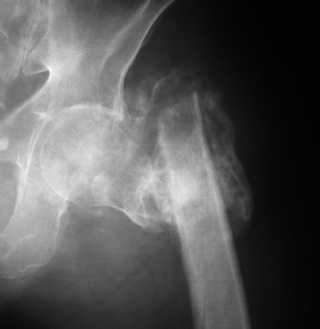

Вот снимки по свежей ситуации, парень 19 лет, длинный оскольчатый перелом бедра от шейки до в-с/3. давно уже ходит на своих ногах.

Представленные Вами рентгенограммы действительно являются примером качественной фиксации спице-стержневым аппаратом. Они, как ни что другое, многое иллюстрируют.

Кроме того, было бы ошибкой ставить знак равенства между нашим и Вашим пациентами. Они не только не похожи, разница между ними просто огромная. Говорю это не для того, чтобы задеть Вас или обидеть. Ни в коем случае. Просто теперь я понимаю, что Ваше мнением строится на простом преломлении Ваших подходов к лечению пациентов со свежими переломами, на ситуацию, абсолютно несопоставимую, подобную нашей.